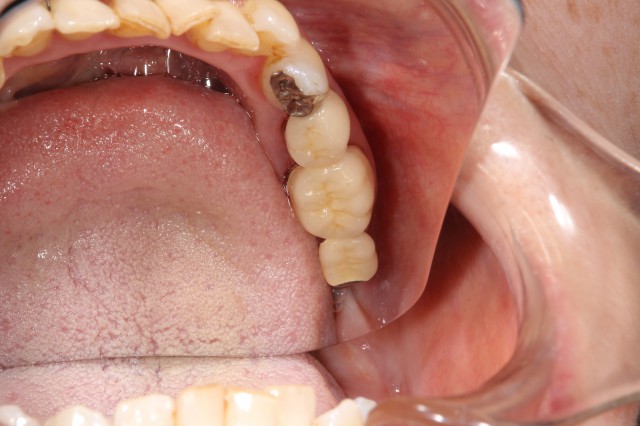

施術前